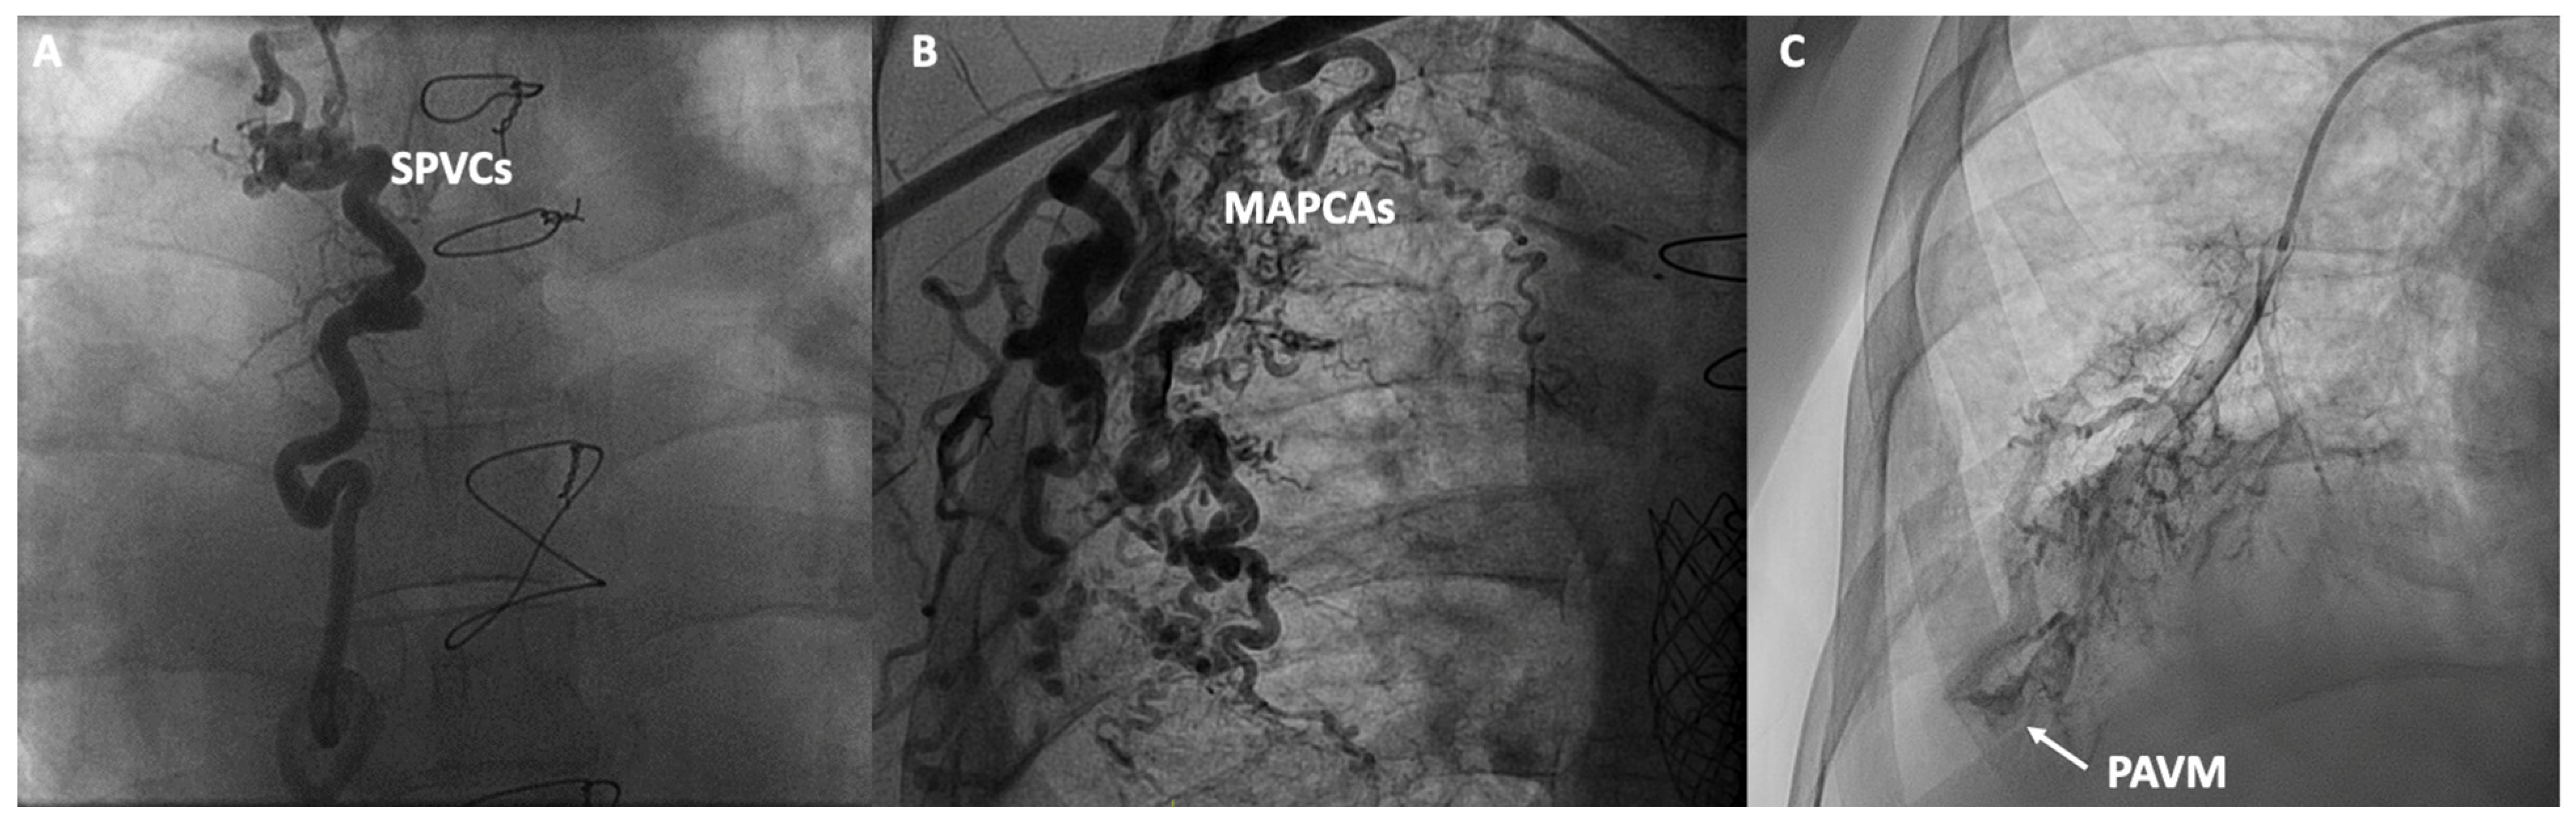

Figure 3.

Contrast angiographic studies: (A) Systemic to pulmonary venous collaterals (SPVCs); (B) Major aortopulmonary collateral arteries (MAPCAs); (C) Macrovascular pulmonary arteriovenous malformation (PAVM).

In addition to functional evaluation, catheterization allows for anatomical assessment through contrast angiography studies aimed at evaluating various structures and anomalies associated with Fontan. In the venous territory, angiographies of the inferior and superior vena cava can be conducted, along with selective angiographies of the pulmonary arteries or the azygos system, aiming to detect obstructions, stenoses, the presence of unknown fenestrations, systemic-to-pulmonary venous collaterals (SPVCs), or pulmonary arteriovenous malformations (PAVM). In the arterial territory, aortography can be performed to assess the presence of aortic insufficiency, coarctations, or MAPCAs. In specific cases, ventriculography can evaluate the presence of atrioventricular valve insufficiency or the systolic function of the single ventricle (Figure 3). However, non-invasive imaging using cardiac magnetic resonance, ultrasound and cardiac CT have displaced classic angiographic studies [53].

2.4. Intrapulmonary Shunts

The assessment of intrapulmonary shunts via angiography is limited, with the exception of macrovascular PAVM (Figure 3). To identify diffuse and microvascular PAVM, which are much more common, agitated saline is selectively administered into each pulmonary artery to prevent contamination due to fenestrations or SPVCs, and echocardiography is observed to assess the presence of bubbles in the ventricle. Severity is graded as non-mild, moderate, or severe, with the latter two indicating PAVM [54].